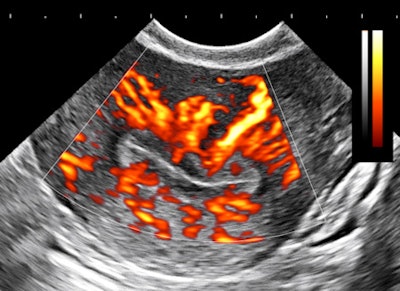

The importance of image contrast is demonstrated in these endovaginal images of a 36-year-old nulliparous woman with heavy and irregular periods due to adenomyosis.

| Above and below: Endovaginal images of a 36-year-old nulliparous woman with heavy and irregular periods due to adenomyosis. |

Adenomyosis (i.e., gland tissue in muscle) occurs when the integrity of the endometrial boundary is disrupted and rapidly growing, vigorous endometrial cells migrate from the city to the myometrial suburbs. Glandular tissue is highly vascularized, leading to the typical 2D Doppler findings with the clinical presentation of heavy, often painful menstruation with clots. There may be small secretory cysts.

The border zone irregularities reconcile the ultrasound findings with pathology and with the classic sign of hysterosalpingography for this condition. This is a grayscale contrast issue. Over the years, I have come to regard contrast as the most important determinant of image quality for all applications of ultrasound.